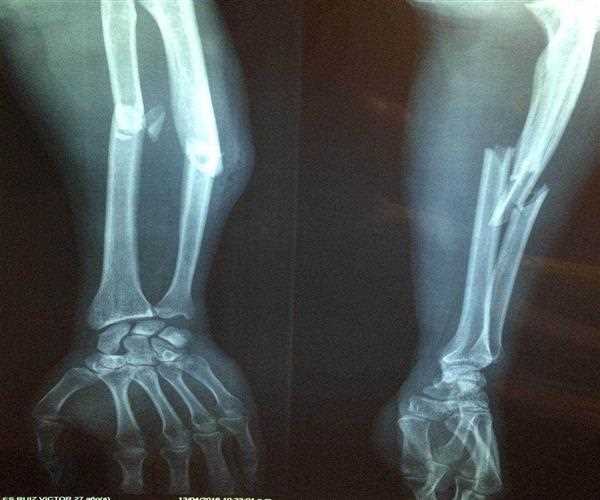

Spiral Fractures: Treatment

Most spiral fractures require surgery and general anesthesia. Less severe cases where the bone is not completely cut can be operated under local anesthesia.

If both ends of the bone are separated, internal fixation surgery is required.

In this procedure, the surgeon usually cuts the skin to expose the fracture. Next, inspect the entire area for floating fragments of bone, broken blood vessels, and tissue damage before recalibrating or reducing the fractured portion of bone.

If necessary, reinforce the bone with pins, screws, or rods to keep the bone aligned during healing. If the surgery includes augmentation, it is called open reduction with internal fixation surgery.